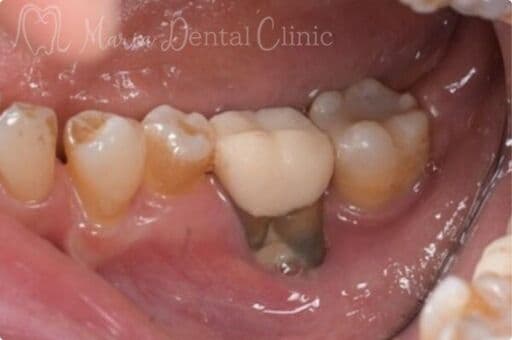

サイナスリフトの症例

【症例】サイナスリフトで骨を増やし、奥歯の支えを回復したインプラント治療

本症例の患者様は、右側の歯を抜歯した後そのまま放置していたことで噛み合わせが大きく乱れ、右上の歯周病が進行して抜歯に至りました。抜歯後は上顎洞に近接して骨量が著しく不足していたため、サイナスリフトによって新たな骨を増やし、インプラントを支える土台を再建しました。十分な骨量を確保することで、奥歯の咬合支持を回復した症例です。

症例から言えること

本症例は、抜歯後の欠損部を放置すると歯が傾斜し、咬合支持が失われることで噛み合わせ全体が乱れ、別の部位の歯周病が急速に悪化することを示しています。さらに、こうした連鎖は将来的な大きな咬合崩壊につながる可能性があります。一方、骨量不足があってもサイナスリフトによりインプラントを支える骨を再建することで、機能を回復し、咬合の安定を取り戻すことが可能です。複雑な症例ほど、早期の診査・診断と適切な処置が咬合崩壊を防ぐ鍵となります。